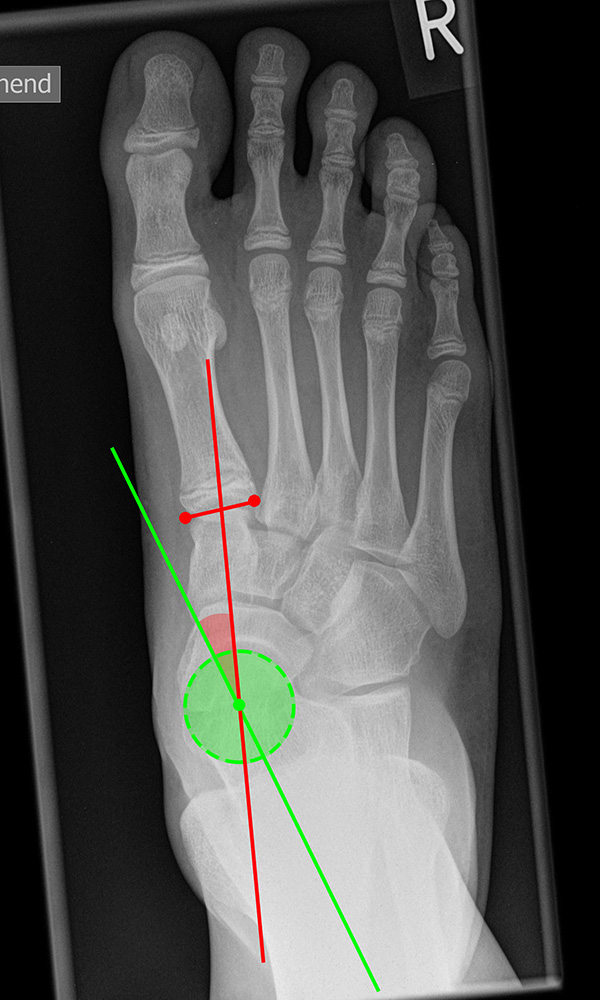

Vermessung der belasteten Aufnahmen des Fußes

Winkelmessungen am Fußskelett beziehen sich sämtlich auf belastete Aufnahmen 6. Die folgenden Aufnahmen zeigen die üblicherweise verwendeten Winkelmaße und ihre Definition. Viele Fehlstellungen des Fußes betreffen den Vor- und Rückfuß. Dies sollte bei der Beurteilung der Bilder und der Therapieplanung stets berücksichtigt werden.

Beurteilung von Fehlstellungen des Vorfußes

Zur Vollansicht und zum Lesen der Bildbeschreibung bitte die Bilder anklicken.

Gelenkflächenwinkel

DMAA (Distal metatarsal artikular angle, Syn. Gelenkflächenwinkel): Winkel zwischen der Achse des Os metatarsale I (rot) und dem Lot auf die distale Gelenkflächenebene (blau) des Os metatarsale I. Die Gelenkflächenebene (grün) wird definiert durch zwei Punkte, welche die mediale und laterale Begrenzung der Gelenkfläche definieren (Norm: <10° 5). Die Projektion des DMAA ist stark abhängig von der Rotation des Os metatarsale I 7. Daher ist bei der operativen Behandlung des Hallux valgus eine Beurteilung häufig erst nach Korrektur der Pronationsstellung des Os metatarsale I möglich. Tendenziell wird der DMAA auf präoperativen Röntgenaufnahmen überschätzt.

Beurteilung eines Metatarsus adductus

Medial wird eine Linie von der medialen Begrenzung des TMT1-Gelenks und der medialen Begrenzung des Talonavikulargelenks (TN) gezeichnet. Auf der lateralen Seite des Fußes wird eine zweite Linie von der lateralen Begrenzung des Calcaneocuboid-Gelenks (CC) zur lateralen Begrenzung des TMT5-Gelenks gezeichnet. Die Mittelpunkte beiden Linien werden verbunden (blau). Der Winkel zwischen der Achse des Os metatarsale II (rot) und dem Lot auf Verbindungslinie (grün) ist ein Maß für die Stellung des Vorfußes zur Fußwurzel. Dieser Wert dient zur Charakterisierung eines Pes adductus. Ein Pes adductus kann zu einem normwertigem Intermetatarsale I/II Winkel führen, obwohl klinisch eine ausgeprägte Hallux valgus Deformität vorliegt 8. (Norm: ±13° 9.

TMT-1-Gelenk dorsoplantar (Tarsometatarsale-1-Gelenk)

In der dorsoplantaren Aufnahme kann ein Versatz der Gelenkfläche im TMT-1 Gelenk auf eine Instabilität hindeuten. Phasenweise wurde auch die Ausrichtung der distalen Gelenkfläche des Os cuneiforme I (grün) zur Achse des Os cuneiforme I (blau) als Risikofaktor diskutiert, hat sich aber aufgrund der starken Projektionsabhängigkeit nicht bewährt 10. (Norm 0-15° 9).

TMT-1-Gelenk lateral (Tarsometatarsale-1-Gelenk)

In der Seitaufnahme wird eine plantare Öffnung des TMT-1-Gelenks als Indikator für eine Instabilität gewertet. Coughlin et al. 5 definierten einen Winkel zwischen der proximalen Gelenkfläche des Os metatarsale I (gelb) und der distalen Gelenkfläche des Os cuneiforme I (rot). (Norm: ±0° 5).